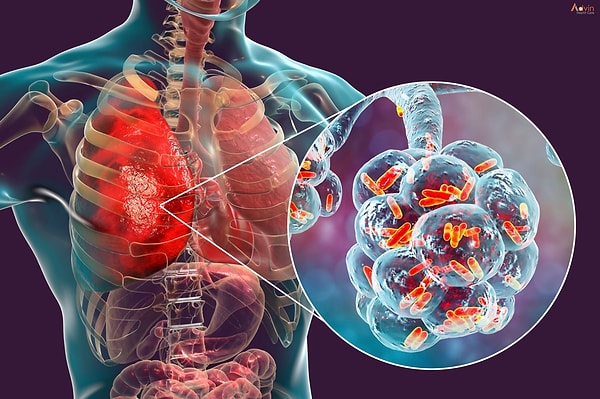

Amerika Birleşik Devletleri'nde bir dönem 'Beyaz Veba' olarak anılan tüberküloz vakaları son on yılın zirvesine ulaştı. Sağlık uzmanları, antibiyotiklere dirençli yeni türlerin COVID-19'dan daha yüksek bir ölüm riski taşıdığı konusunda acil uyarıda bulunuyor.

Amerika Birleşik Devletleri, tıp dünyasının geçmişte kaldığını düşündüğü "Beyaz Veba" yani tüberkülozun (verem) korkutucu dönüşüyle sarsılıyor.

Hastalık Kontrol ve Önleme Merkezleri (CDC) tarafından paylaşılan son veriler, vaka sayılarının son 10 yılın en yüksek seviyesine ulaştığını kanıtlıyor. Uzmanlar, bu artışın sadece bir rakamdan ibaret olmadığını, hastalığın artık mevcut ilaçlara karşı çok daha dirençli ve yıkıcı bir forma büründüğünü vurguluyor.

Tarihte kurbanlarını aşırı solgun bıraktığı için bu isimle anılan tüberküloz, akciğerleri hedef alarak vücudu adeta içten içe tüketiyor. Dr. Robert Redfield gibi önemli isimler, tüberkülozun doğru tedavi edilmediği senaryolarda koronavirüsten çok daha yüksek bir öldürme oranına sahip olduğuna dikkat çekiyor. Modern varyantların tedaviye yanıt vermemesi, sağlık otoritelerini küresel bir kriz ihtimaline karşı harekete geçirmiş durumda.

Bu tehlikeli geri dönüşün arkasında ise birden fazla kritik neden yatıyor. COVID-19 pandemisi döneminde sağlık kaynaklarının tamamen virüse yönelmesi, verem taramalarının ve rutin kontrollerin aksamasına yol açtı. Bunun yanı sıra artan küresel hareketlilik, bağışıklık sistemini zayıflatan kronik stres ve mevcut antibiyotiklerin etkisiz kaldığı 'MDR-TB' olarak bilinen dirençli türlerin yayılması, salgının fitilini ateşleyen temel unsurlar olarak görülüyor.